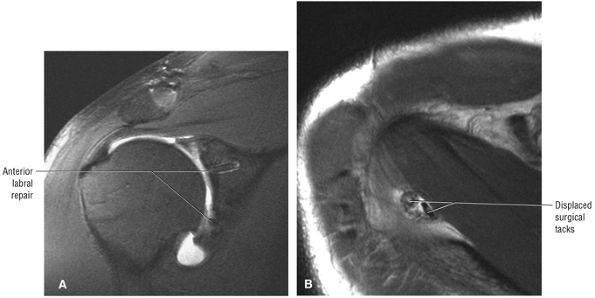

Postoperative evaluation of repaired labral capsular structures and/or strictures, recurrent rotator cuff tears or partial tears, and displaced hardware

ABER (abduction external rotation) images in conjunction with MR arthrography are helpful in evaluating the postoperative labrum and nondisplaced (e.g., Perthes) labral tears.